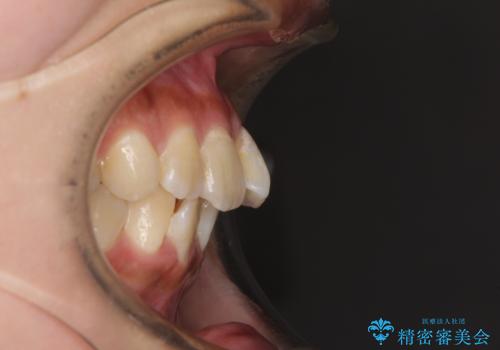

歯列は叢生が認められる程度でしたが、やや前突感があったので、少しでも口が閉じやすくなるように仕上げる方針としました。

神経を取り除かれている歯3本以外にも虫歯が認められたため、事前に処置を行い、インビザラインにて矯正治療を行うこととしました。

神経が取り除かれている歯は、クラウンによる補綴治療が必要であるため、矯正治療後にオールセラミッククラウンにて補綴治療を行うこととしました。

歯磨きしやすくなるとともに、飛び出していた前歯も引っ込めて整えることができました。